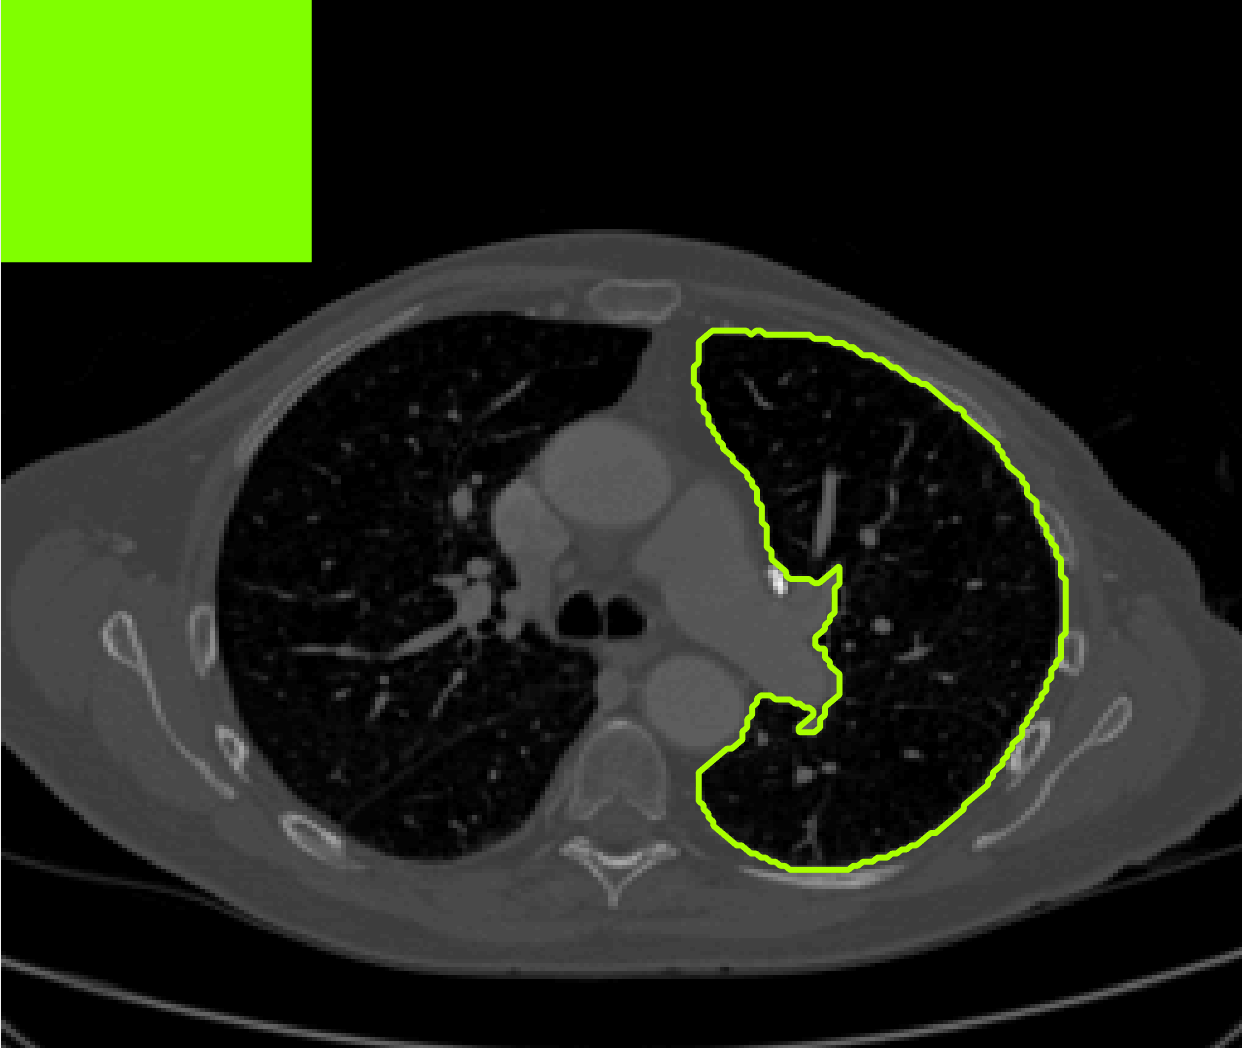

for and as defined in (33). This is consistent with respect to the intensities of the observed object and the concept of selective segmentation. In Fig. 3 we see the difference between CV and the proposed fitting terms for given user input on a CT image. For the CT image, the CV fitting terms are near 0 within the target region. This is despite there being a distinct homogeneous area with good contrast on the boundary. This illustrates the problem we are aiming to overcome. With the proposed fitting term this phenomenon should be avoided in cases like this. By defining as in (33) there is no contradiction if the foreground and background intensities of the target region are similar.